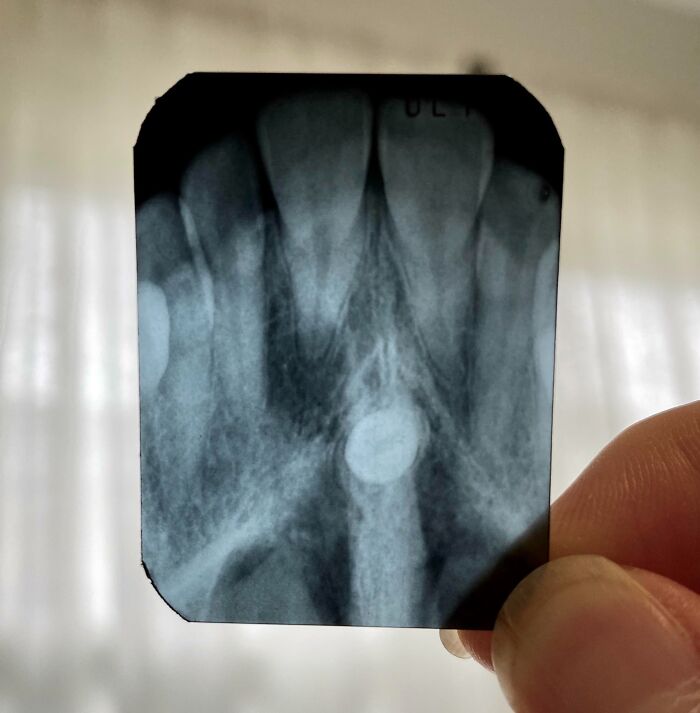

#16 My 6-Years-Old's Dental X-Ray

Image credits: 15926028